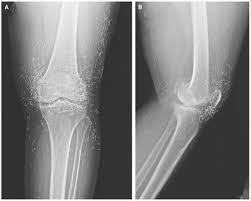

Tính truyền thẳng và đâm xuyên: Tia X truyền thẳng và có khả năng xuyên qua vật chất, qua cơ thể người. Sự đâm xuyên này càng dễ dàng khi cường độ tia càng tăng. Chính vì độ xuyên sâu của tia X cao nên người ta dùng để chụp những bộ phận cứng như: xương, răng, không dùng để chụp mô

Chụp X quang không chuẩn bị bao gồm các kỹ thuật chụp X quang các bộ phận của cơ thể như chụp xương khớp, chụp bụng, chụp sọ não, chụp cột sống, chụp phổi, chụp hệ tiết niệu.v.v. không sử dụng được chất cản quang.